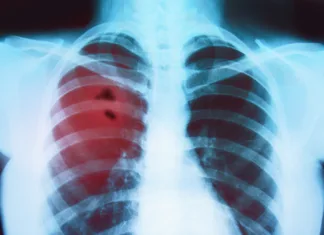

Rak pljuč: prvi bolnik prejel cepivo

Prvi bolnik z rakom pljuč v UCLH je prejel novo cepivo proti raku, namenjeno spodbujanju imunskega sistema za prepoznavanje in boj proti rakavim celicam....